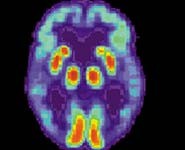

Press release issued 6 December 2010 - Scientists in Bristol have uncovered some of the processes responsible for the blood flow problems connected with Alzheimer's disease. Their findings could see existing drugs used for leaky blood vessels trialled as potential Alzheimer's treatments. Researchers at the University of Bristol's Dementia Research Group supported by the Alzheimer's Research Trust , the UK's leading dementia research charity, investigated problems with the function of blood vessels in the brains of people with Alzheimer's ' a known feature of the disease. Scientists already know that in Alzheimer?s, blood vessels in the brain do not adjust properly in response to changes in brain activity and blood pressure. The vessels also become too permeable, allowing potentially harmful substances to leak into the brain from the bloodstream. In a new series of studies, PhD student Emma Ashby, Professor Seth Love and Dr Patrick Kehoe found marked abnormalities in the system that helps to regulate blood vessel function in people with Alzheimer?s. Their findings are published in the journals Brain Research and Neurobiology of Aging .